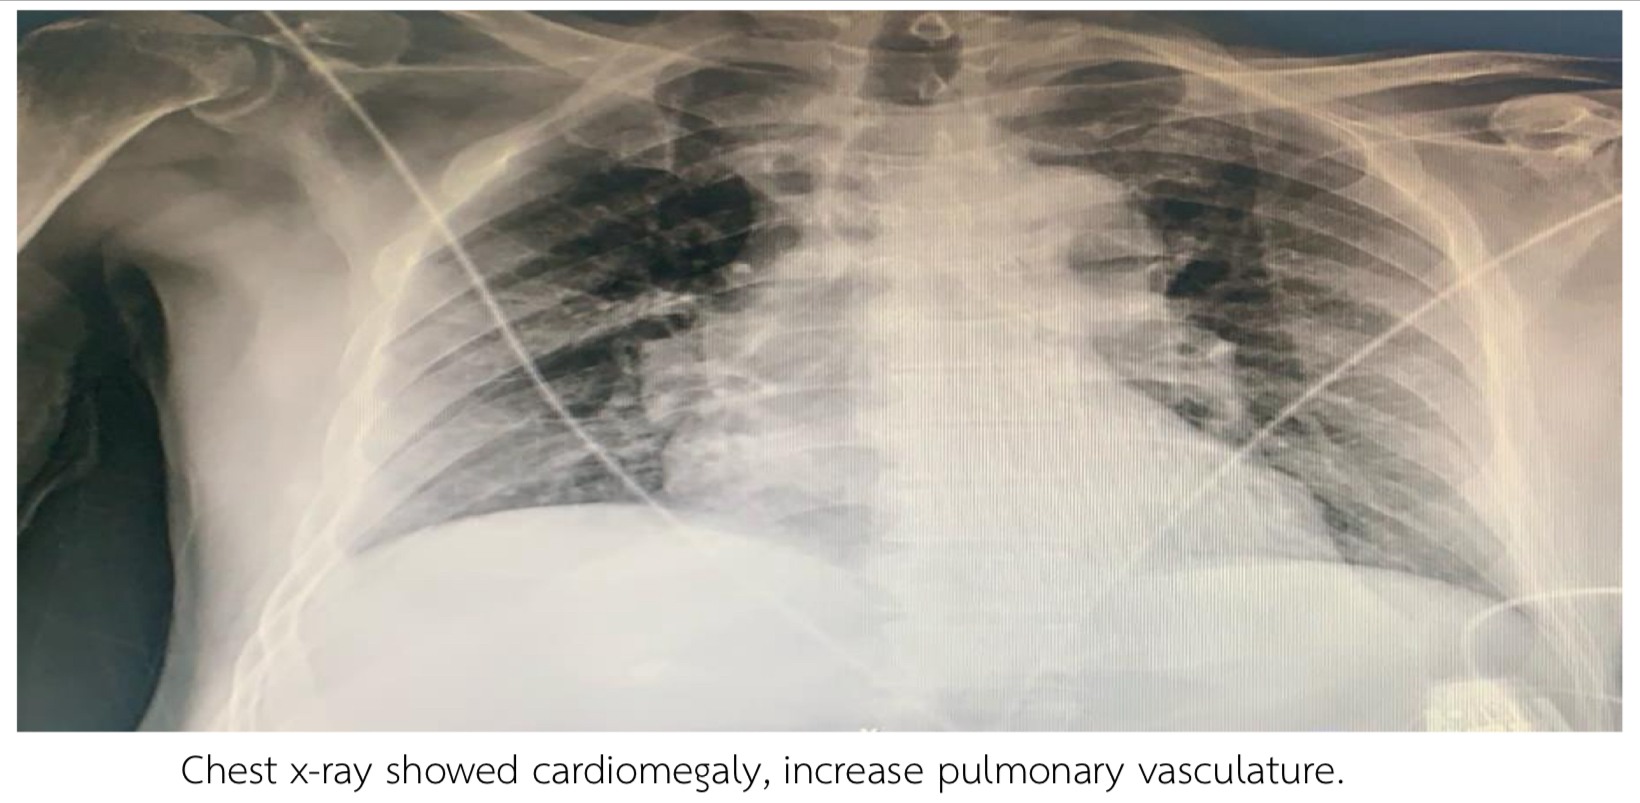

Thai male 69 years, Risk HT, DLP presented with chest pain 2 hours prior to admission. BP 104/62 mmHg HR 76 bpm. Heart regular, fine crepitation both lower lungs. EKG showed NSR, 84 bpm, STE II, III, AVF, diffused STD V2-V6. Echo showed LVEF 42%, Global wall Hypokinesia, no significant VHD. Troponin T was positive 10,400 pg/ml. Chest x-ray showed cardiomegaly, increase pulmonary vasculature.

EKG showed NSR, 84 bpm, STE II, III, AVF, diffused STD V2-V6. Echo showed LVEF 42%, Global wall Hypokinesia, no significant VHD. Troponin T was positive 10,400 pg/ml. Chest x-ray showed cardiomegaly, increase pulmonary vasculature.